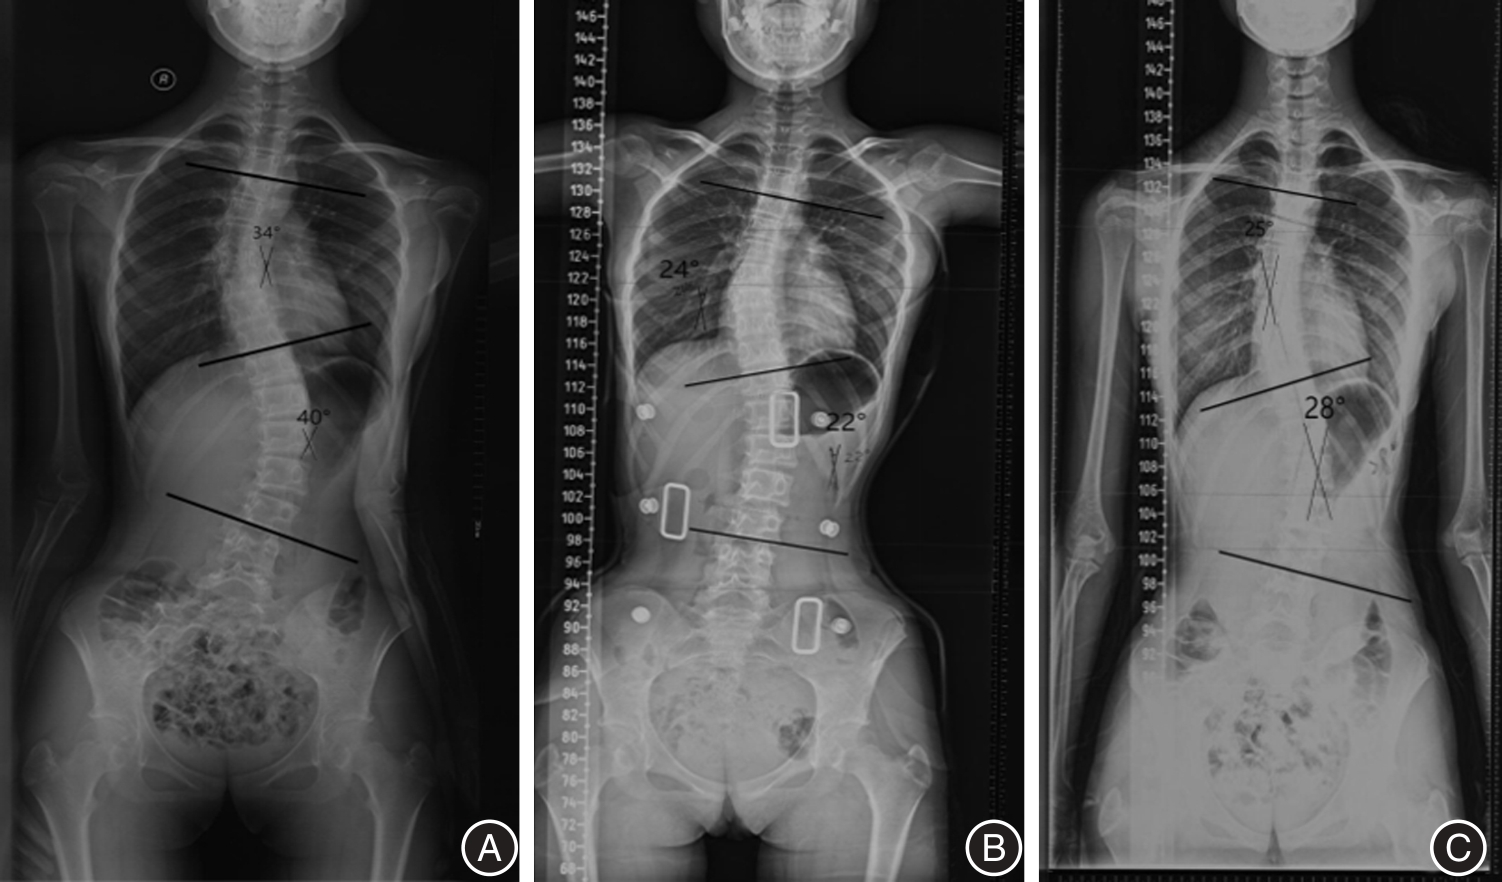

Objective To evaluate the efficacy of Schroth PSSE combined with 3D printing braces in the treatment of adolescent idiopathic scoliosis. Method Forty patients were included and divided into a support group (3D printing support group) and a support + exercise therapy group (3D printing support + Schroth PSSE group). Excluding outliers and lost follow-up data, 32 patients were ultimately included, with 16 patients in each group. Wearing time ≥ 18 h for both groups of 3D printing supports. The intervention period of Schroth PSSE is 12 weeks, and exercise is maintained after 12 weeks until the end of follow-up. The longest follow-up time for the brace group was 25 months, with an average follow-up time of (15.00 ± 1.29) months. The longest follow-up time for the brace+exercise therapy group was 24 months, with an average follow-up time of (16.59 ± 1.01) months. Relevant indicators were evaluated after follow-up. Results The support and exercise therapy group showed better improvement in Cobb angle and trunk rotation angle (ATR) than the support group, with statistically significant differences (P < 0.05); The distance between the midpoint of the C7 vertebral body and the midline of the sacrum (C7-CSVL) in the support and exercise therapy group showed a statistically significant difference before and after treatment (P < 0.05), while there was a significant difference before and after Apical Vertebral Translation(AVT )treatment (P < 0.01). There was no statistically significant difference compared to the support group (P < 0.05); In terms of SRS-22 score, the brace + exercise therapy group can comprehensively improve the SRS-22 score. Conclusion The combination of Schroth PSSE and 3D printing braces has a better effect on improving Cobb angle and torso rotation angle, improving coronary imbalance, increasing patient satisfaction, and improving quality of life compared to using 3D printing braces alone.